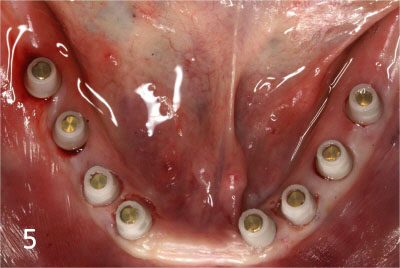

Totally edentulous status on lower jaw

Fit surgical guide for precise implant placement

Removal of gum at exact site for implant placement with dental laser

Placing Implants

Connection of temporary cylinder for provisional bridge

Provisional bridge to use right after placing implants

This is after bonding provisional bridge. Patient can have strong teeth in a few hours